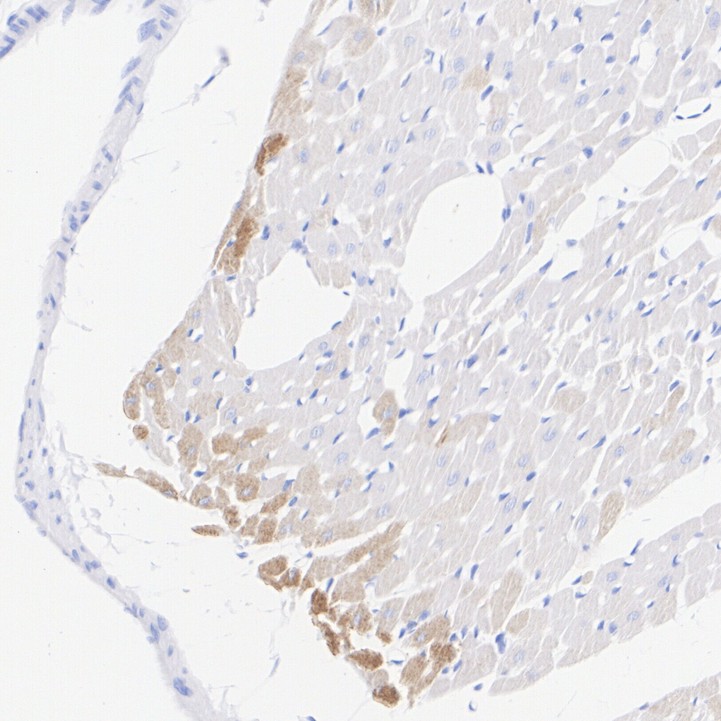

Slow Skeletal Myosin Heavy chain Recombinant Rabbit Monoclonal Antibody [PSH07-54] - BSA and Azide free

Catalog# HA751092

IHC-P